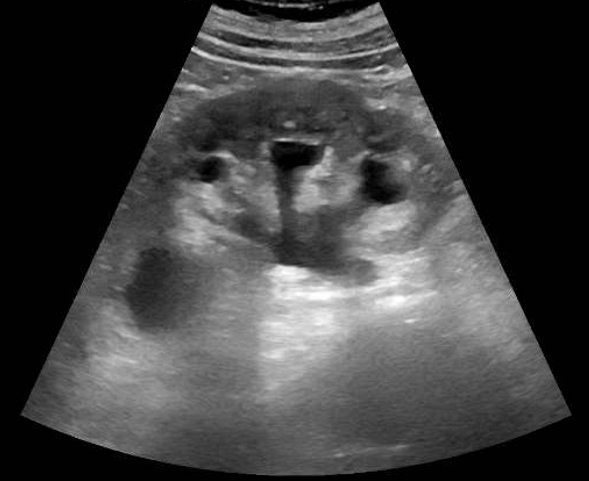

Hombre de 69 años. Antecedentes personales: diabetes mellitus tipo 2, hipertensión arterial, hipercolesterolemia.Acude a Urgencias por astenia progresiva de un mes de evolución y recorte de diuresis. Exploración: palidez mucocutánea. Normotenso y eupneico. Auscultación cardiorespiratoria normal. Abdomen globuloso, blando, no doloroso. Analítica: Hb 9 (previa 11 dos meses antes), urea 160, creatinina 10,9 (previa 1,7), proteína C reactiva 120. Resto anodino (no leucocitosis ni alteraciones iónicas, urianálisis negativo). EFNa: 14% (posrenal). Ecografía renal, que evidencia hidronefrosis bilateral grado III, sin causa obstructiva aparente. Dada la evolución tórpida pese a sueroterapia y diuréticos, se realiza TAC abdominal para continuar estudio de la causa obstructiva: aneurisma de aorta abdominal infrarrenal, con rotura contenida por hematoma y compresión extrínseca de ambos uréteres.

Respecto a la Ecografía, es esencial una sistemática de exploración minuciosa para mayor rentabilidad diagnóstica. La generalización del uso de la ecografía Atención Primaria y en Urgencias supone un diagnóstico más rápido y preciso, y por tanto una mejor atención al paciente.